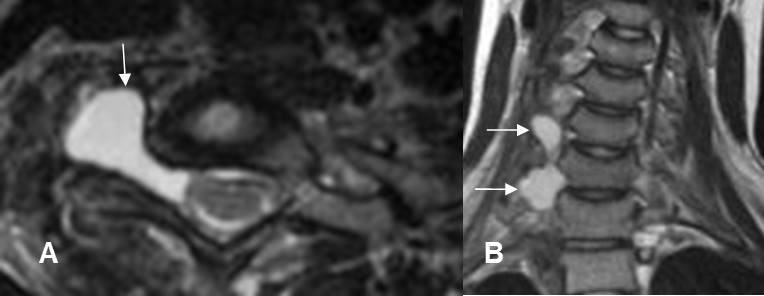

Fig 144. Ruptura de raíces.

A: RM axial y B: RM coronal en T2. Formación de seudomeningoceles en el lado derecho, por avulsión de las raíces.